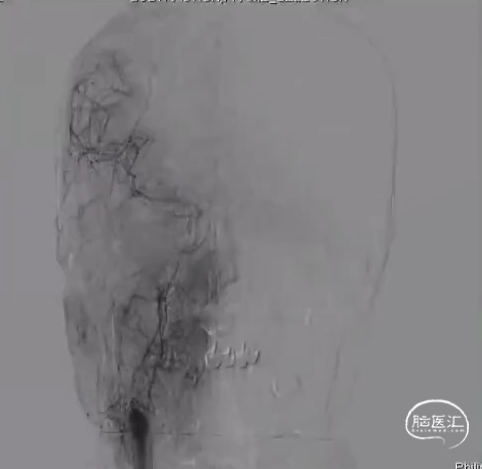

术后DSA R-CCA